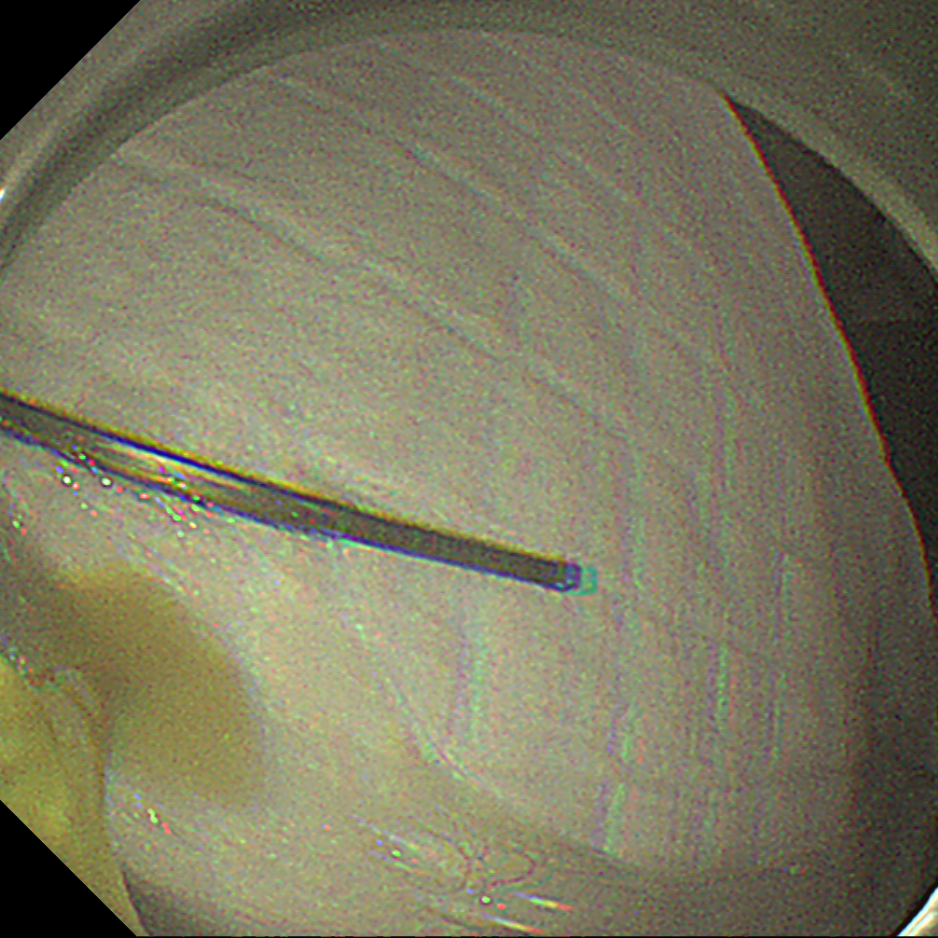

小肠里的「不速之客」:多镜接力巧取铁钉

小朋友误吞铁钉,送到消化内科时医生发现已进入小肠深处。内镜团队首先使用小肠镜将铁钉拖回胃内,但因其表面光滑、头端尖锐,难以安全通过食管。随后,医生果断更换方案,用加装了透明帽的胃镜,将铁钉尖锐的一端套入帽内,最终将其平稳、安全地经食管取出。